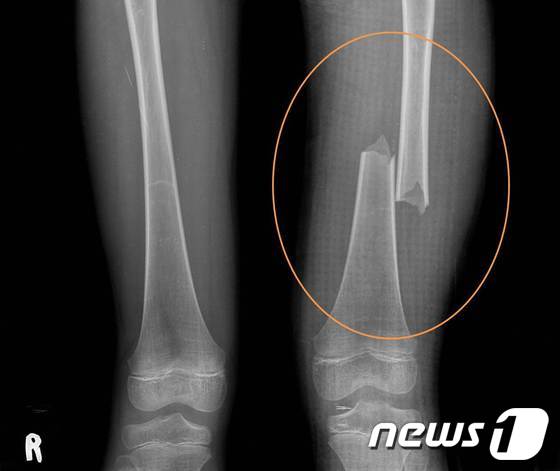

▲2012년 5월 21일 : 7세였던 피해자의 허벅지를 발로 수차례 걷어차 대퇴부 골절되게 해 상해